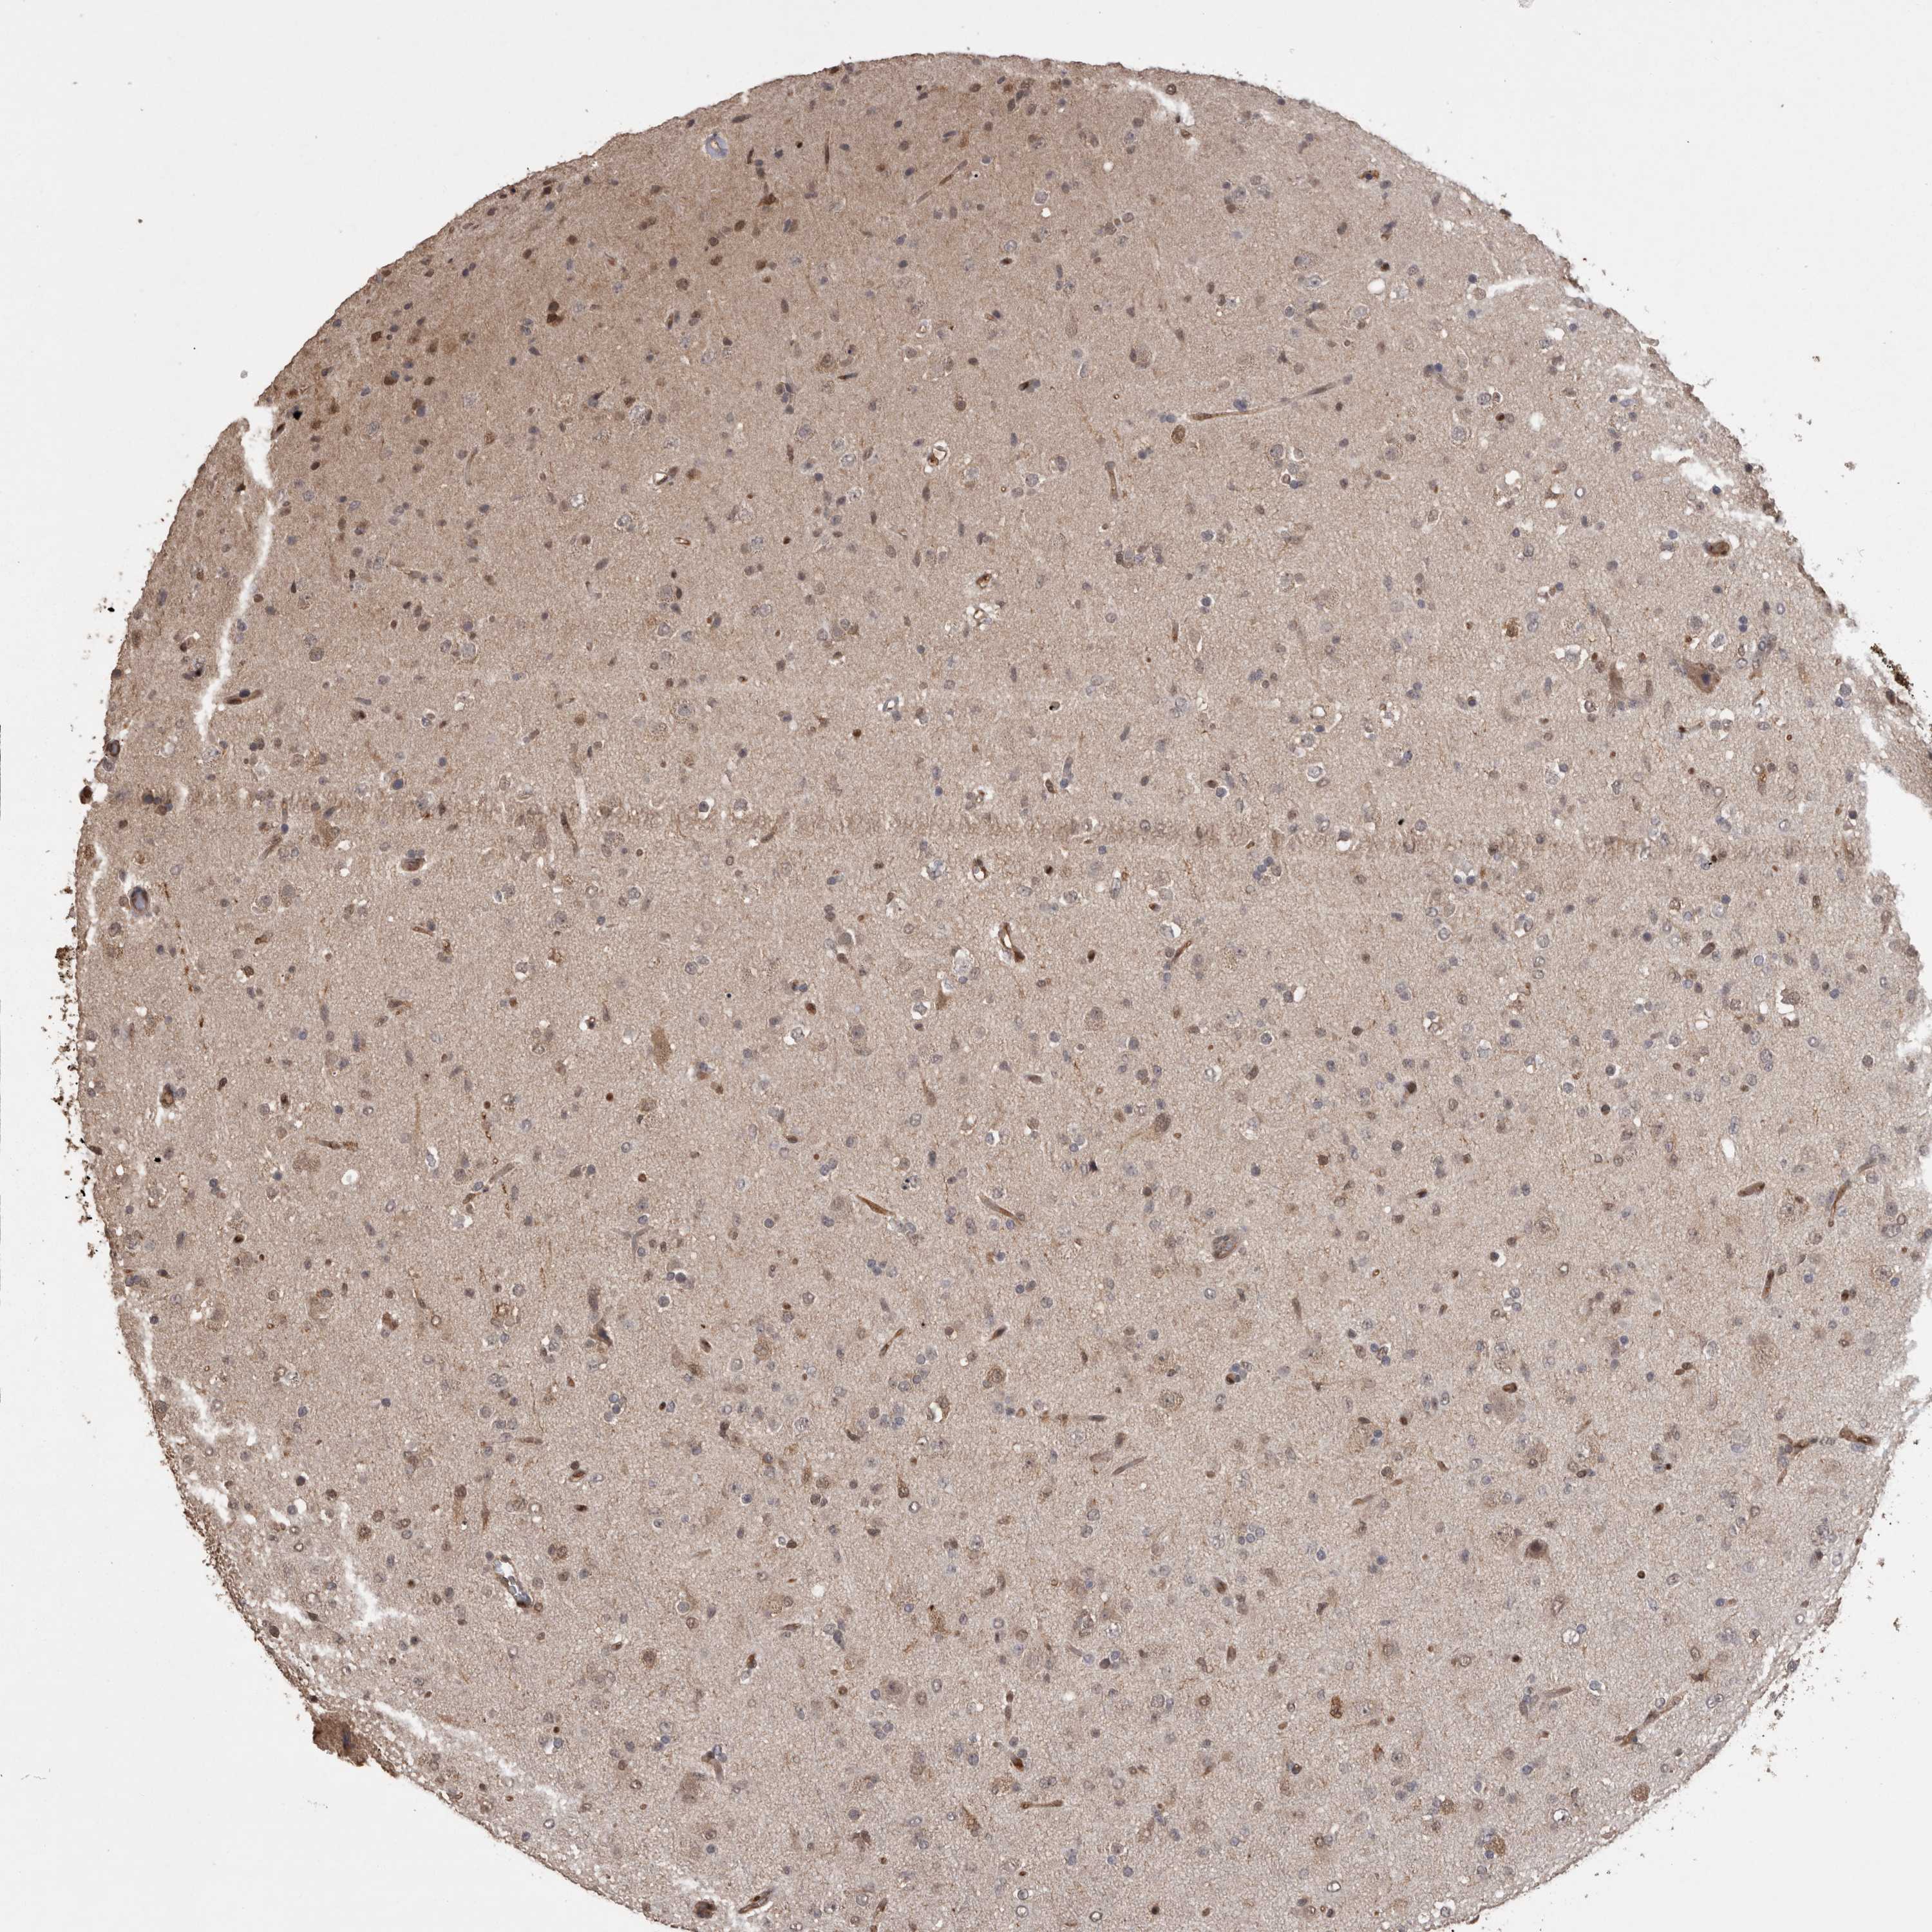

GLIOMA - Protein expressioni

A mouse-over function shows sample information and annotation data. Click on an image to view it in a full screen mode. Samples can be filtered based on level of antibody staining by selecting one or several of the following categories: high, medium, low and not detected. The assay and annotation is described here.

Note that samples used for immunohistochemistry by the Human Protein Atlas do not correspond to samples in the TCGA dataset.

Antibody stainingi

Antibody staining in the annotated cell types in the current human tissue is reported as not detected, low, medium, or high, based on conventional immunohistochemistry profiling in selected tissues. This score is based on the combination of the staining intensity and fraction of stained cells.

Each image is clickable and will lead to virtual microscopy that enables deeper exploration of all samples and also displays staining intensity scores, fraction scores and subcellular localization as well as patient and tissue information for each sample.

Antibody HPA014179

Antibody CAB025128

Staining

High

Medium

Low

Not detected

Intensity

Strong

Moderate

Weak

Negative

Quantity

>75%

75%-25%

<25%

None

Location

Nuclear

Cytoplasmic/membranous

Cytoplasmic/membranous,nuclear

Glioma, malignant, High grade

Glioma, malignant, Low grade